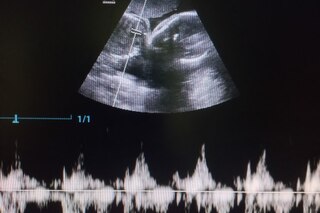

Однако при осмотре стало ясно, что естественные роды не начнутся. В ходе ультразвукового исследования в полости матки было обнаружено четыре щенка. При этом, у одного из них выявили брадикардию — замедленную сердечную деятельность.